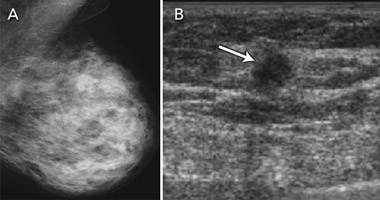

Breast ultrasound examination is not currently endorsed as a population-screening test, but has been applied in clinical practice for ad-hoc screening of women with dense breast tissue on mammography. Breast tissue density refers to the radiodense fibroglandular composition of the breast. High density of breast tissue is a significant and independent risk factor for breast cancer,23,24 and also reduces the sensitivity of mammography, as glandular tissue masks cancer on the mammogram. It is therefore not surprising that high density of breast tissue is associated with greater likelihood of an interval cancer in mammography screening,25 as women with dense breast tissue are both more likely to develop breast cancer and more likely to have cancer missed on mammography.

The accuracy of breast ultrasound examination is unaffected by breast tissue density. Ultrasonography has therefore been evaluated and applied in practice to “screen” women with dense breast tissue26-30 (Box 5). Evidence on its capacity to detect breast cancer in asymptomatic women with “negative” mammograms is summarised in Box 6. These studies provide data on additional (incremental) ultrasound detection — both true-positive and false-positive findings. The studies consistently show that ultrasonography is able to detect a substantial number of cancers in women with mammography-negative dense breast tissue, with additional cancers detected in 0.27%–0.46% of women screened with ultrasound.26-30 The detection capability of ultrasonography in this setting depends partly on how well mammography performs in the population being screened — “negative” mammograms may in fact show a cancer that has not been recognised by the screen-reader. This was demonstrated in a 2008 study that included “blinded” evaluation of the mammograms for ultrasound-only-detected cancers: about a quarter of ultrasound-detected cancers were perceived on the mammogram by an experienced radiologist.29 Another study found that the highest proportion of ultrasound-only-detected cancers (0.46%) occurred in women screened on the basis of dense breasts plus additional risk factors, with more than half of the screened women having a personal history of breast cancer.30 The false-positive rate for ultrasonography is considerable and varies between studies. False-positive results (in terms of both additional investigation and unnecessary surgical intervention) are the main potential limitation of ultrasonography in adjunct population screening.

The data in Box 6 also indicate that ultrasonography was able to detect breast cancers that were not identified in dense breasts on mammography screening at an early stage, generally at a comparable or earlier stage than cancers detected on mammography. This suggests that ultrasonography as an adjunct screening test may provide further benefit in screening women with dense breast tissue. It would thus be valuable to conduct large-scale RCTs of ultrasonography as an adjunct to mammography in screening women with dense breasts, with 2–3-year follow-up, to measure its impact on interval cancer rates. Demonstrating a reduction in interval cancers in women who have adjunct screening (relative to women who have mammography screening only) provides a surrogate indicator of longer-term benefit.11

6 Evidence on ultrasonography (US) in screening asymptomatic women with mammography-negative dense breast tissue